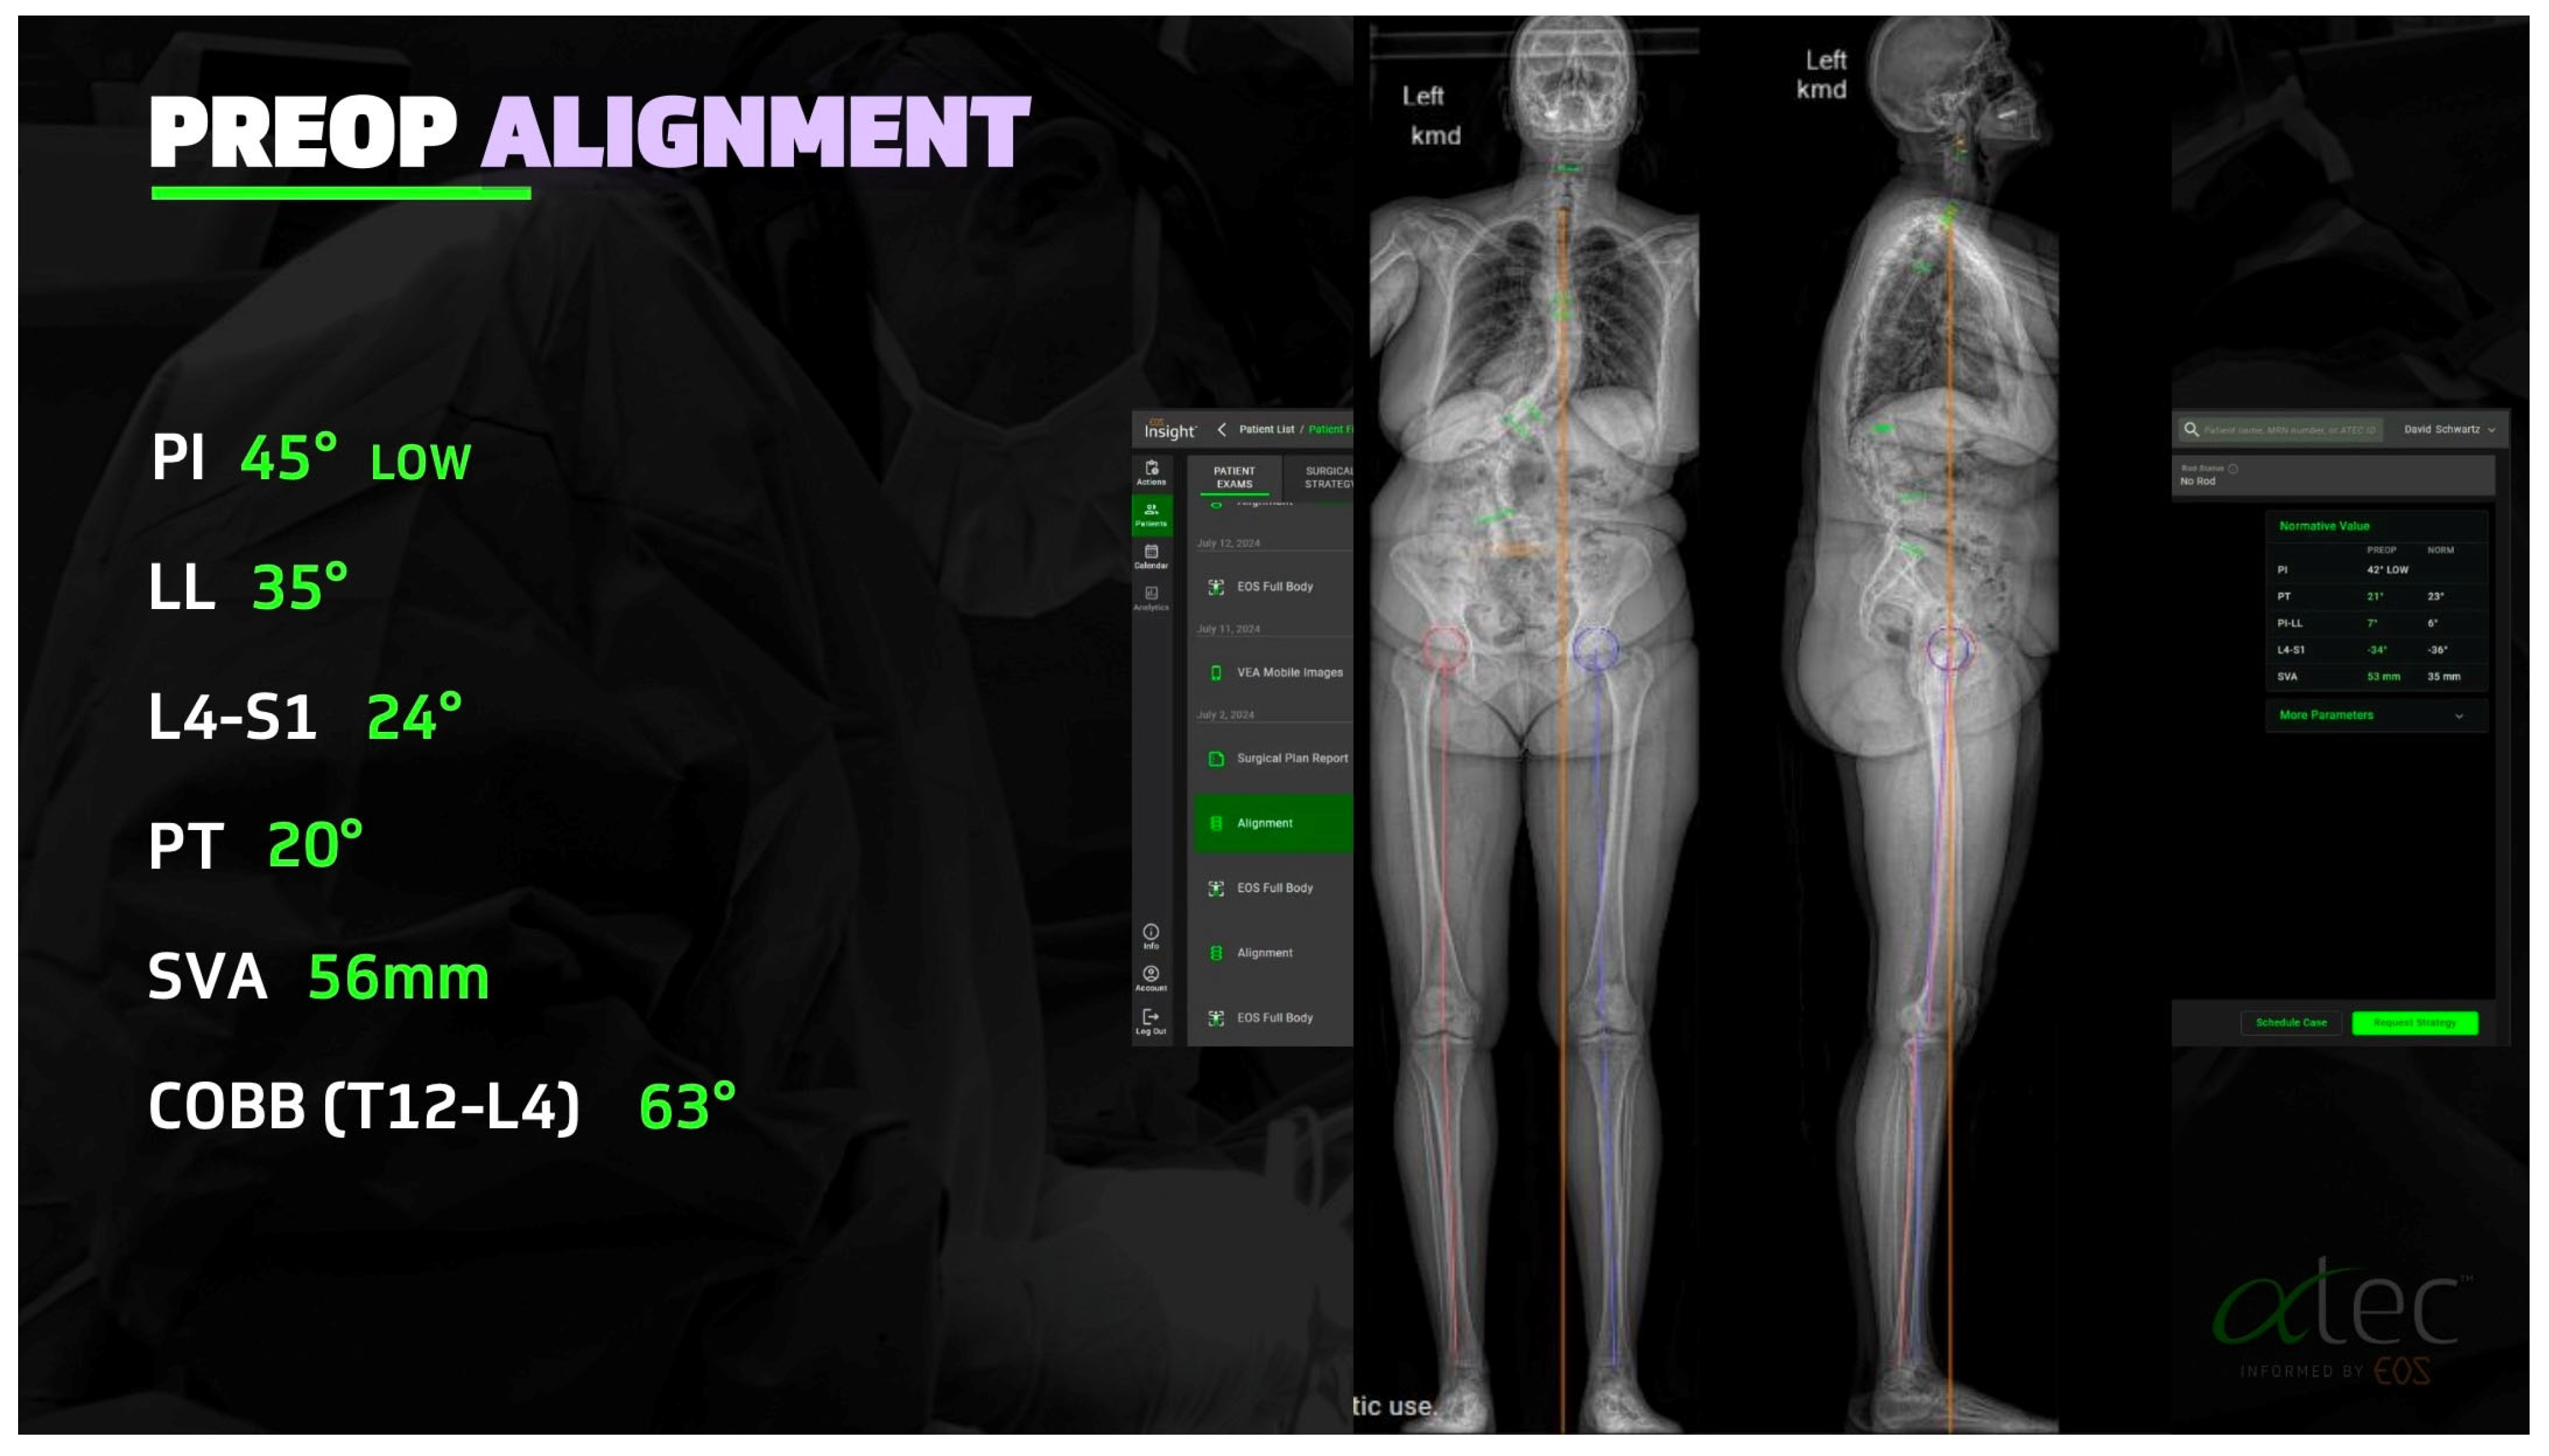

2.1. Advances in Deformity Imaging

2.4. Preoperative Planning and Predictive Modeling